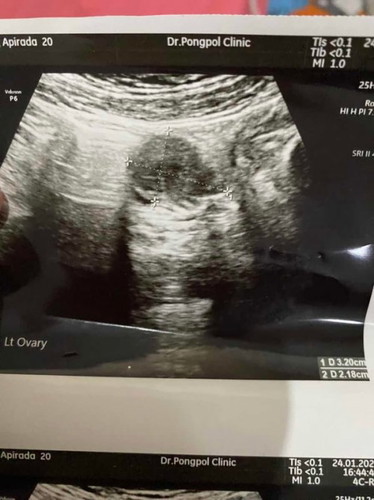

พอดีหนูตรวจขึ้น2ขีดเมื่อวันที่20มกราคม วันนี้เลยจะไปฝากครรภ์ แต่ลุงหมอซาวด์ไม่เจออะไรเลยแม้แต่ถุงตั้งครรภ์

5วีค ซาวหน้าท้องไม่เจออะไรเหมือนกันค่ะ เลยซาวช่องคลอด เจอถุงตั้งครรภ์ที่เล็กมากกก

ลองไปซาวที่คลินิกก็ได้ค่ะบอกหมอขอซาวทางช่องคลอดหนู4วีคเกือบ5เจอค่ะซาวทางช่องคลอด

ทางนี้ก็ 5W ค่ะเพิ่งไปซาวดูเมื่อวานเจอถุงตั้งครรภ์แล้วค่ะ